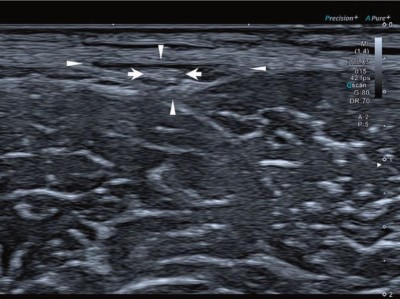

Der letzte Teil der Serie „Kompressionssyndrome der Leiste und der unteren Extremitäten“ behandelt das Morton-Neurom. Als Risikofaktor gilt vor allem das Tragen von unpassendem Schuhwerk, wodurch die Interdigitalnerven chronisch gereizt werden. Insbesondere bei größeren Neuromen sind konservative Maßnahmen nur begrenzt wirksam, weshalb oft eine operative Dekompression des Nervs indiziert ist. …

Das Morton-Neurom

Palpationstest bei Morton-Neurom/© Springer Medizin Verlag GmbH, Aufziehen einer Spritze/© Eisenhans / Fotolia, Junge Ärztin vor einem Triage-Zelt/© Milos / Stock.adobe.com (Symbolbild mit Fotomodell), Tabletten werden in Hand geschüttet/© O.Farion / Stock.adobe.com (Symbolbild mit Fotomodell), Kranker Junge mit erhöhter Temperatur/© Imgorthand / Getty Images / iStock (Symbolbild mit Fotomodell)